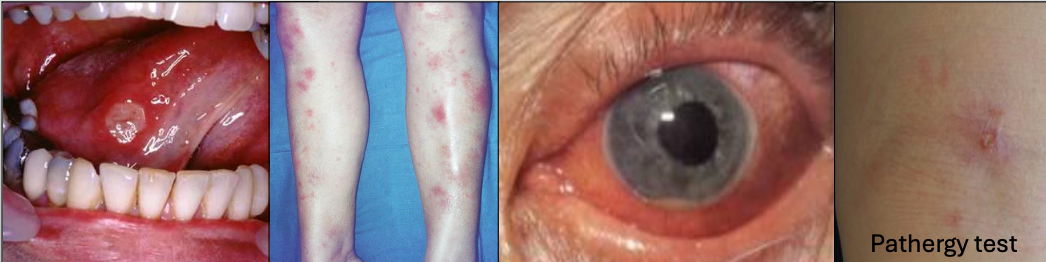

What is Behçet Syndrome?

A chronic recurrent autoimmune disease,20’s and 30’s, Mediterranean or Asian descent (Silk road)

What is the criteria for diagnosis of Behçet Syndrome?

Recurrent oral ulcers 3x/yr + 2 of

Recurrent genital ulcerations (75%)

Eye lesions (70%)

Skin lesions

+ pathergy test (results are variable)

In which condition do you see arthritis

Behçet Syndrome